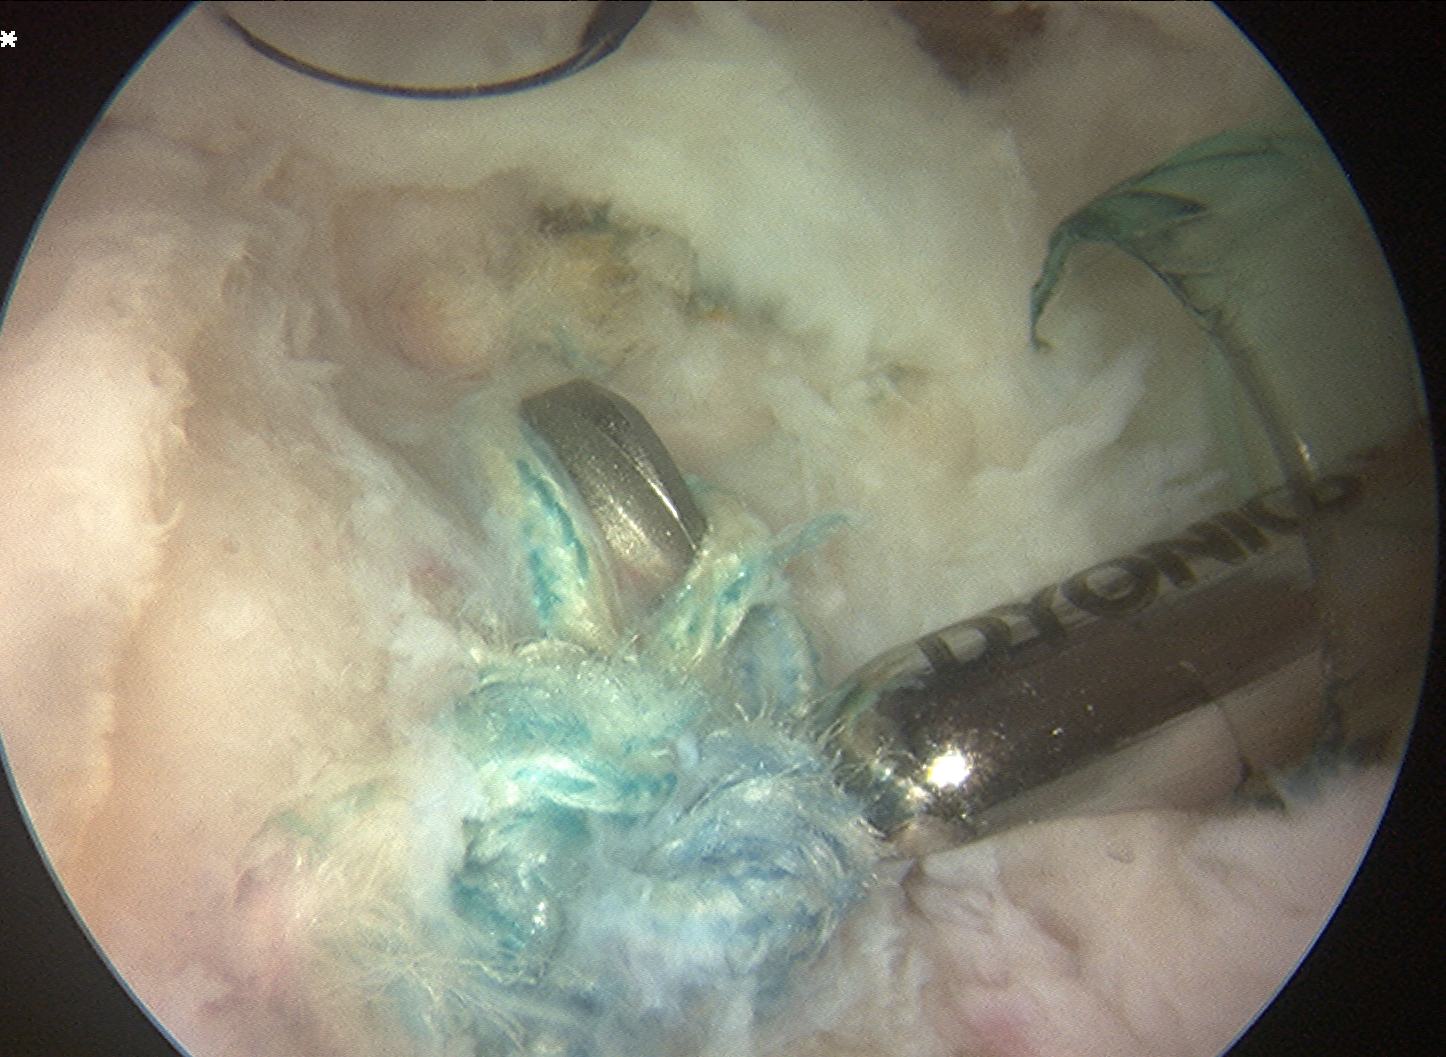

Trans-osseous equivalent / suture bridge

- cross sutures from medial row to lateral row

- increase contact between cuff and footprint

Double row / suture bridge

- use medial row sutures

- secure in knotless lateral row anchors